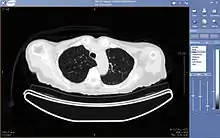

Teleradiology

Teleradiology is the ability to send radiographic images (x-rays, CT, MR, PET/CT, SPECT/CT, MG, US...) from one location to another.[57] For this process to be implemented, three essential components are required, an image sending station, a transmission network, and a receiving-image review station. The most typical implementation are two computers connected via the Internet. The computer at the receiving end will need to have a high-quality display screen that has been tested and cleared for clinical purposes. Sometimes the receiving computer will have a printer so that images can be printed for convenience.

The teleradiology process begins at the image sending station. The radiographic image and a modem or other connection are required for this first step. The image is scanned and then sent via the network connection to the receiving computer.

Today's high-speed broadband based Internet enables the use of new technologies for teleradiology: the image reviewer can now have access to distant servers in order to view an exam. Therefore, they do not need particular workstations to view the images; a standard personal computer (PC) and digital subscriber line (DSL) connection is enough to reach keosys central server. No particular software is necessary on the PC and the images can be reached from wherever in the world.

Teleradiology is the most popular use for telemedicine and accounts for at least 50% of all telemedicine usage.